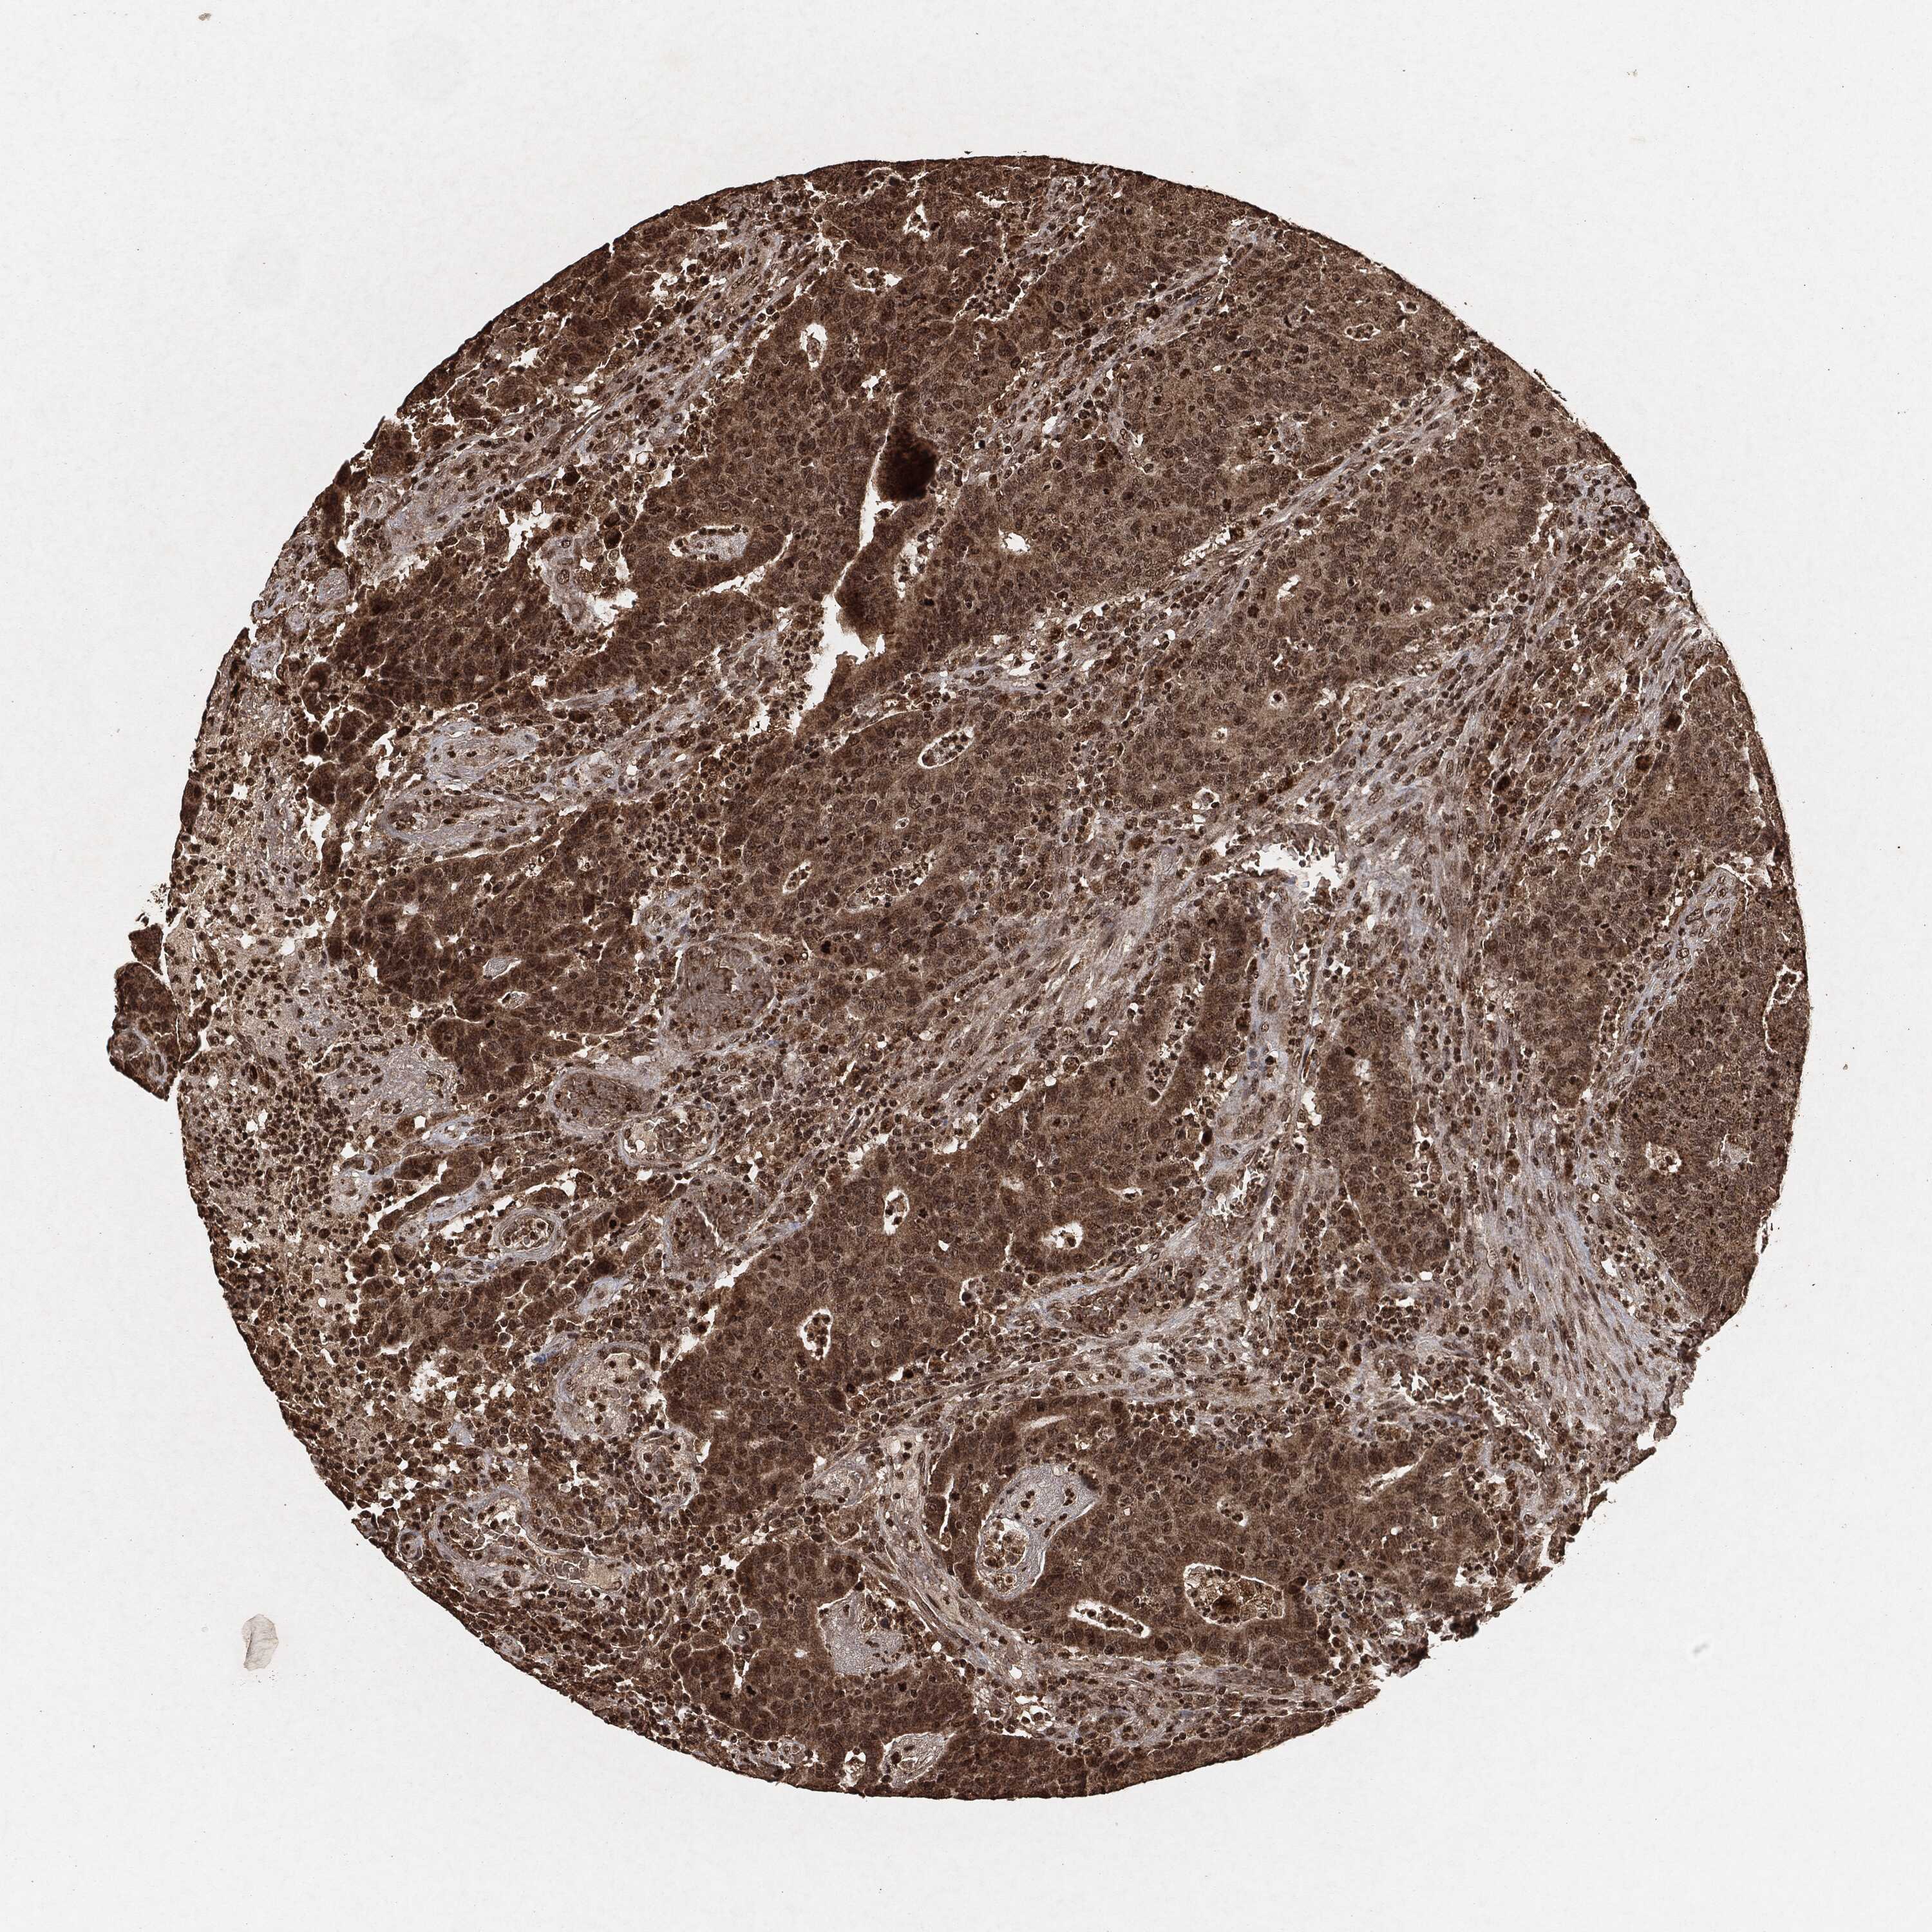

CANCER COLORECTAL CANCER Show tissue menu

Colorectal cancer

Human cancer

Colon adenocarcinoma